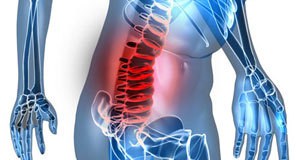

Spinal column surgery solves the most complicated problems which affect the spine and the whole organism.

The spinal column is the basis of human body which enables people to walk upright.

The spinal column consists of vertebrae interspersed with discs which like shock-absorbers enable people to walk upright and to have the right body posture.

The spinal column is lined with muscles on the outer side, while inside the spinal column there is the canal where the spinal cord and nerves are situated.

The spinal column consists of three parts: cervical, thoracic and lumbosacral.